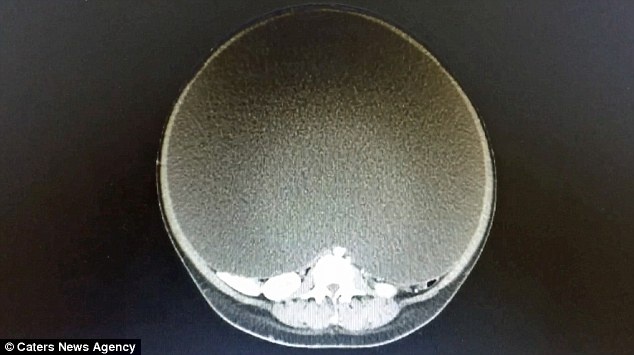

| Bản chụp X quang cho thấy khối u khổng lồ của bệnh nhân. Ảnh: Catters News Agency. |

Tại bệnh viện, các bác sĩ xác định trong ổ bụng của cô có một khối u nang buồng trứng, đường kính 50 cm và chu vi 157 cm. Khối u nang này chiếm đến 95% thể tích của ổ bụng, chèn ép lên các cơ quan nội tạng khiến cô gái gặp rất nhiều khó khăn về hô hấp, ăn uống và đi lại.